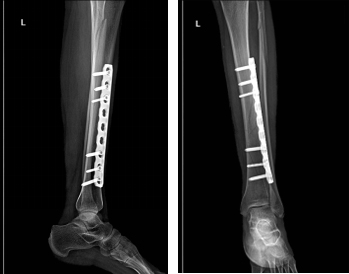

术后X线示:

手术前X线对比,骨折复位良好,对位对线满意,患者下肢力线恢复,对于创伤不稳定骨折,有手术指征的,需尽早手术复位以及坚强合理的内固定装置固定,有利于骨折的早期愈合。